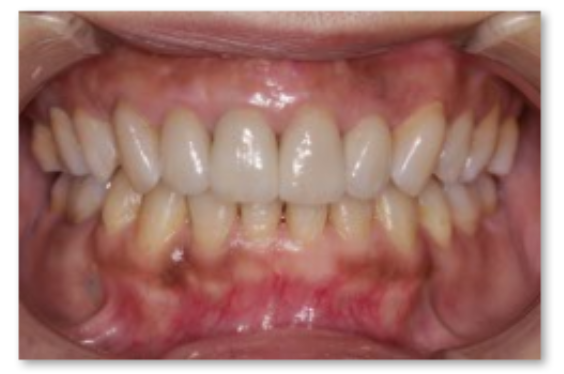

前歯部をオールセラミックによる審美的、機能的な回復をはかったケースです。

前歯ということで歯ぐきのラインにも気をつけより自然な仕上がりにしました。